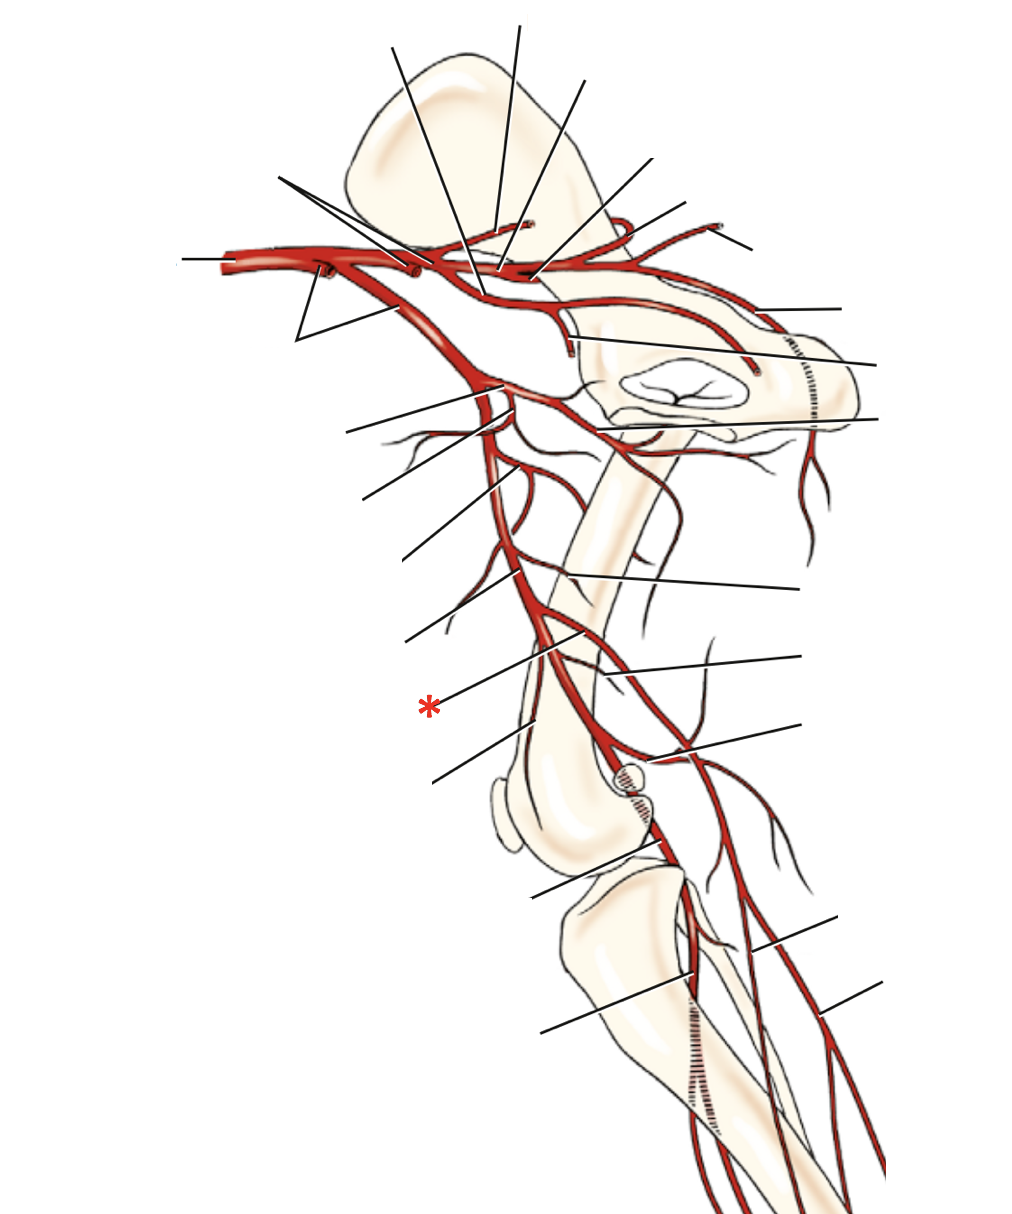

N. tibialis

A. saphena r. caudalis

A. saphena

A. saphena

A./v. saphena

5

V. saphena medialis

16

V. saphena lateralis

V. saphena lateralis r. caudalis

V. saphena lateralis

V. tibialis caudalis

- ex. v. poplitea ex v. femoralis